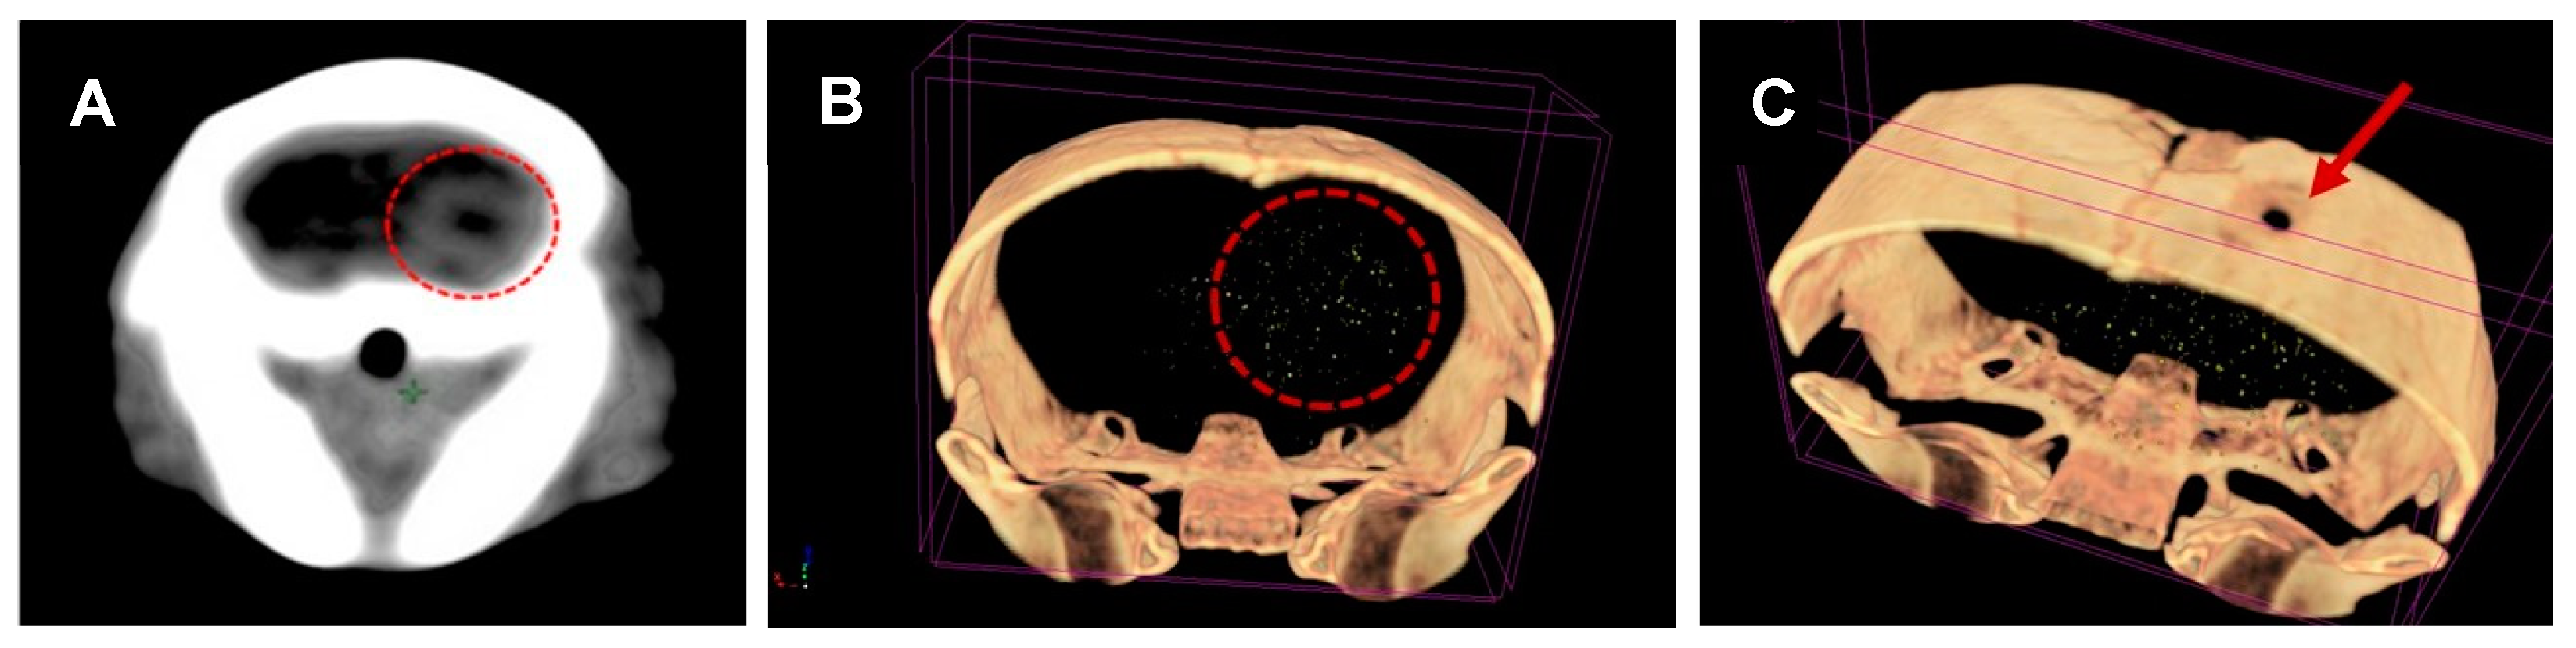

2.5. Micro-CT Scans

3.2. CTX-INS-GNPs Combined with Standard Therapy Inhibits Tumor Progression and Prolongs Survival

3.3. Combined Treatment with CTX-INS-GNPs Eradicates Tumor Cells